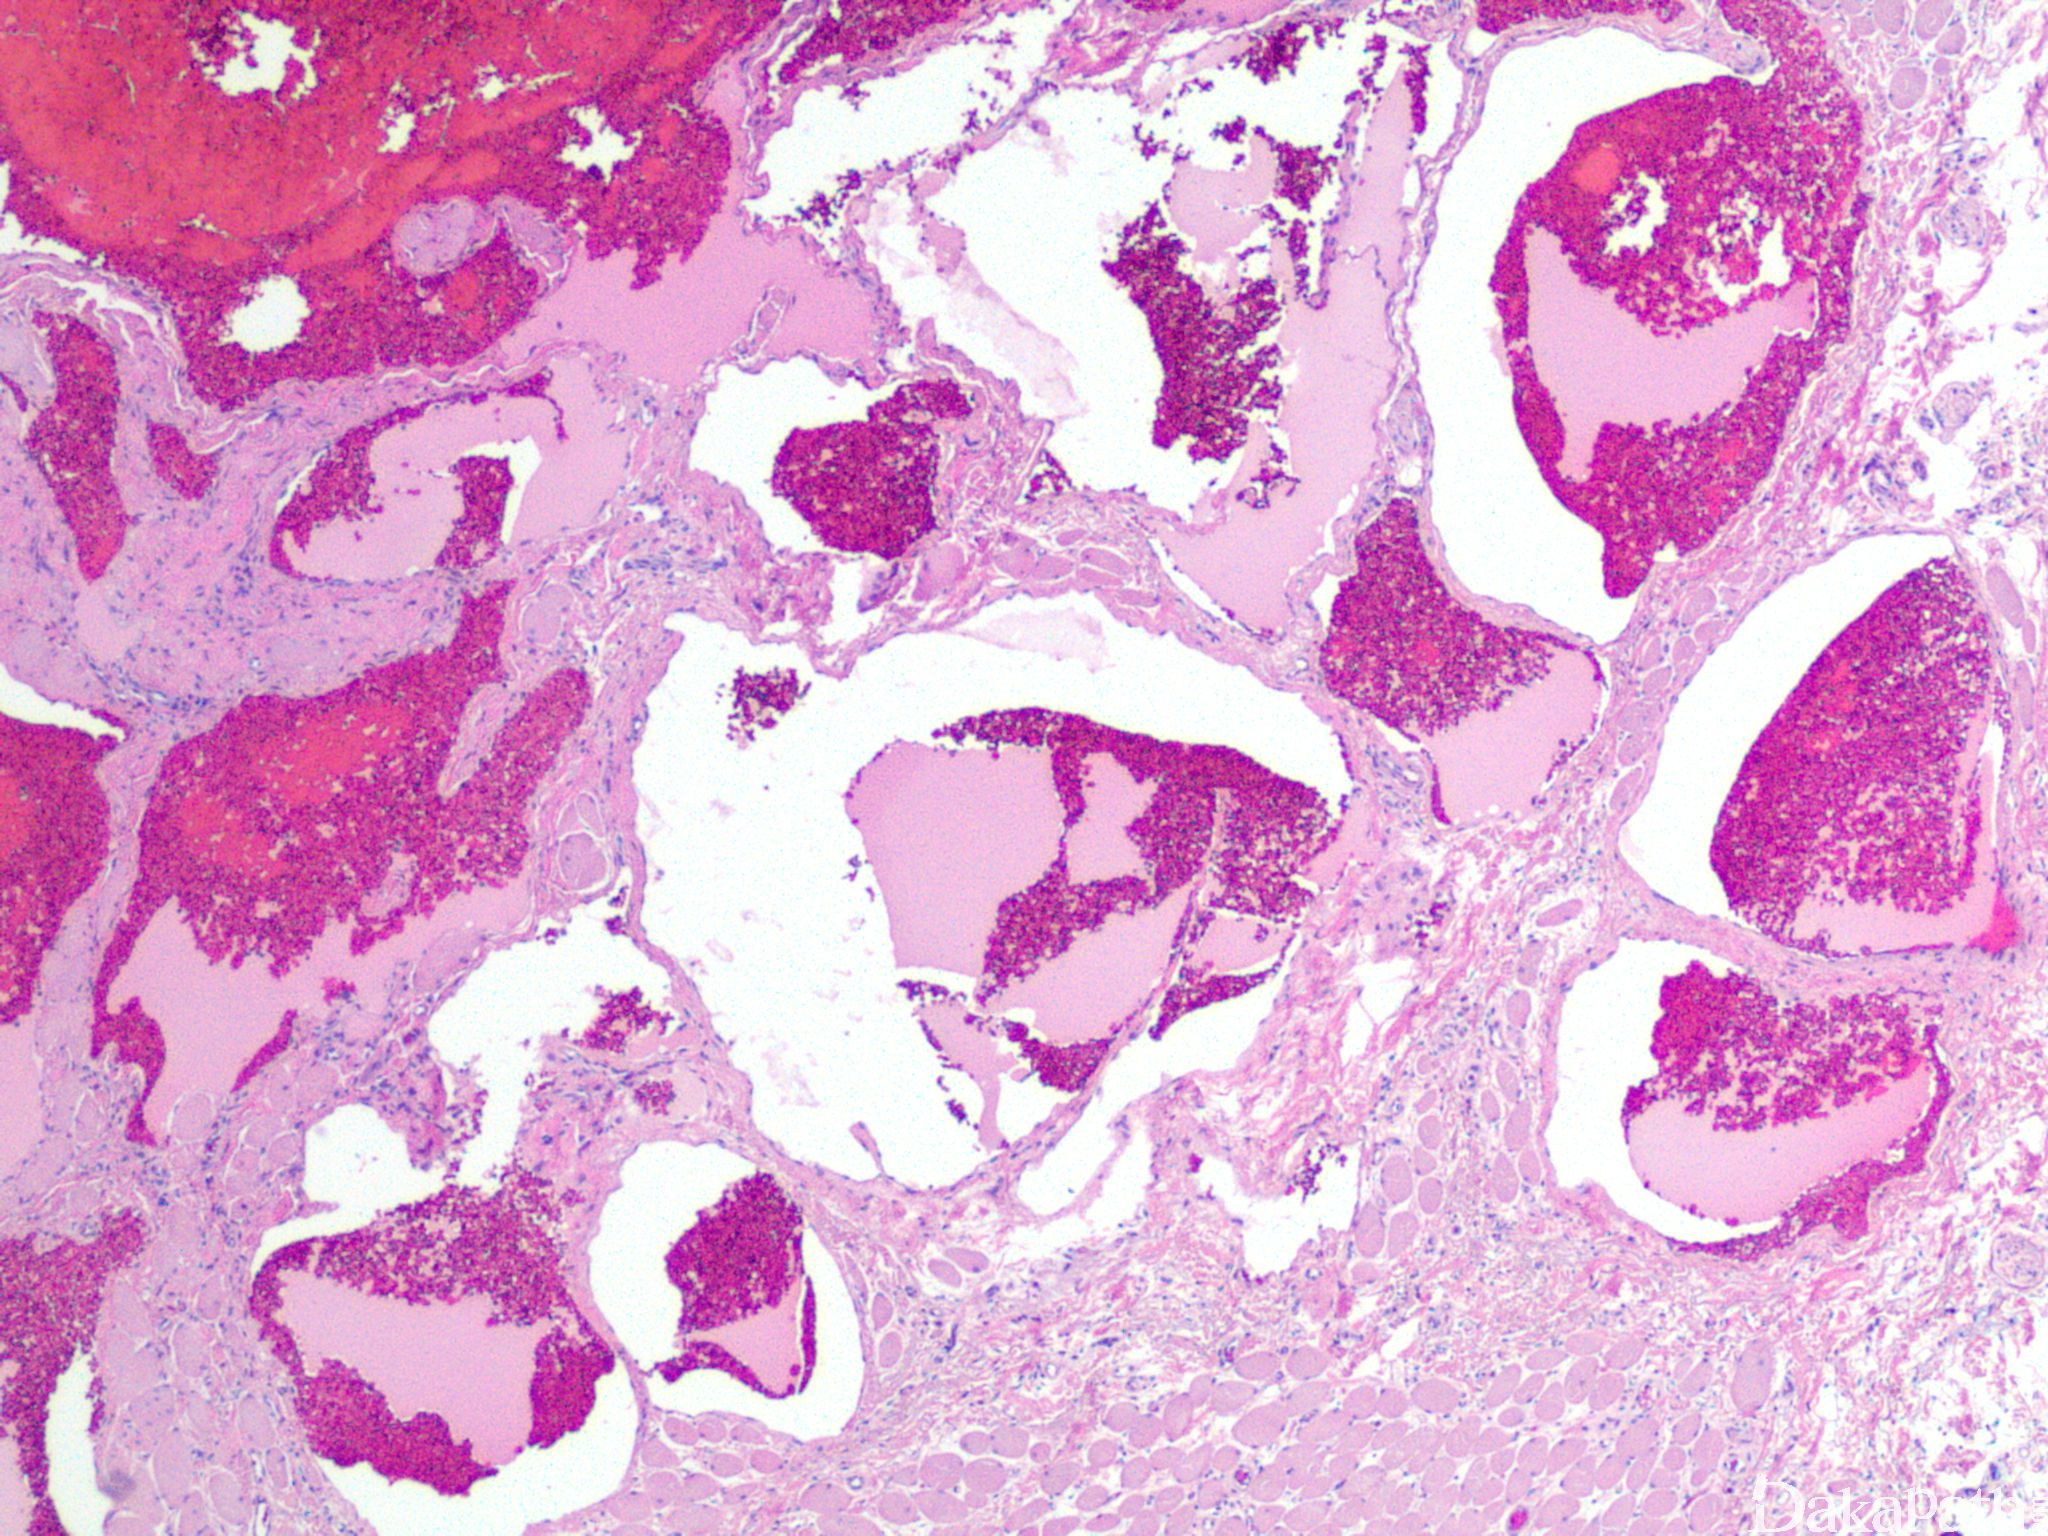

静脉湖

venous lake